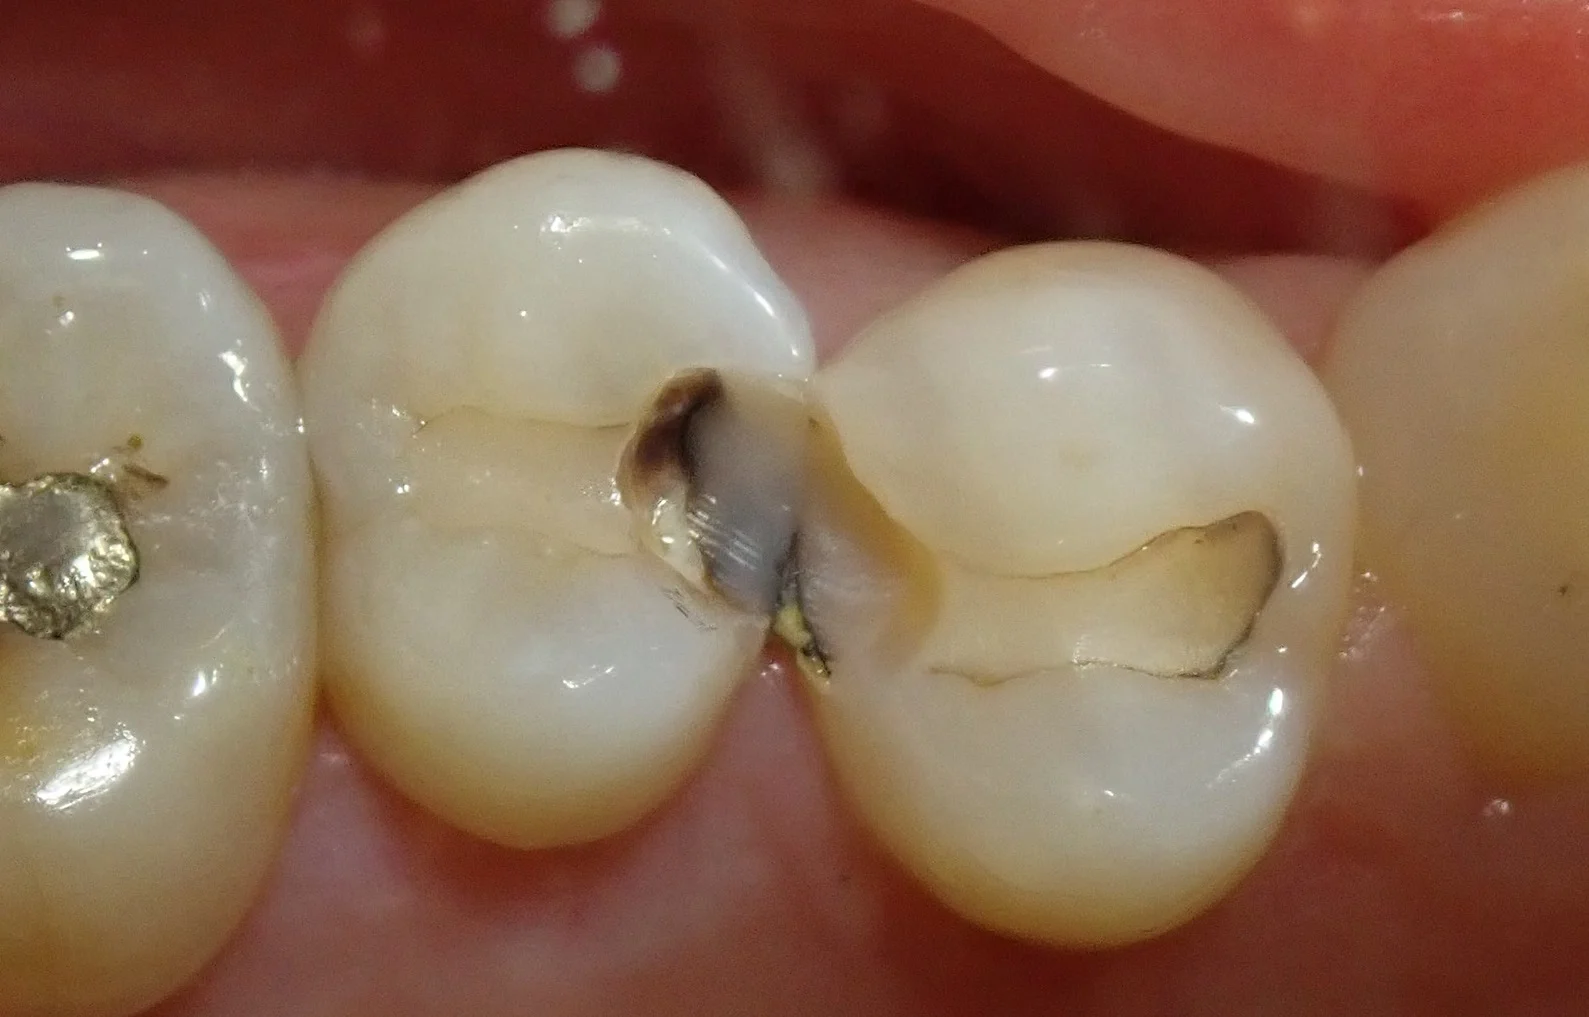

まずは術前

あからさまに詰め物の下が黒くなっているのが分かるかと思います。